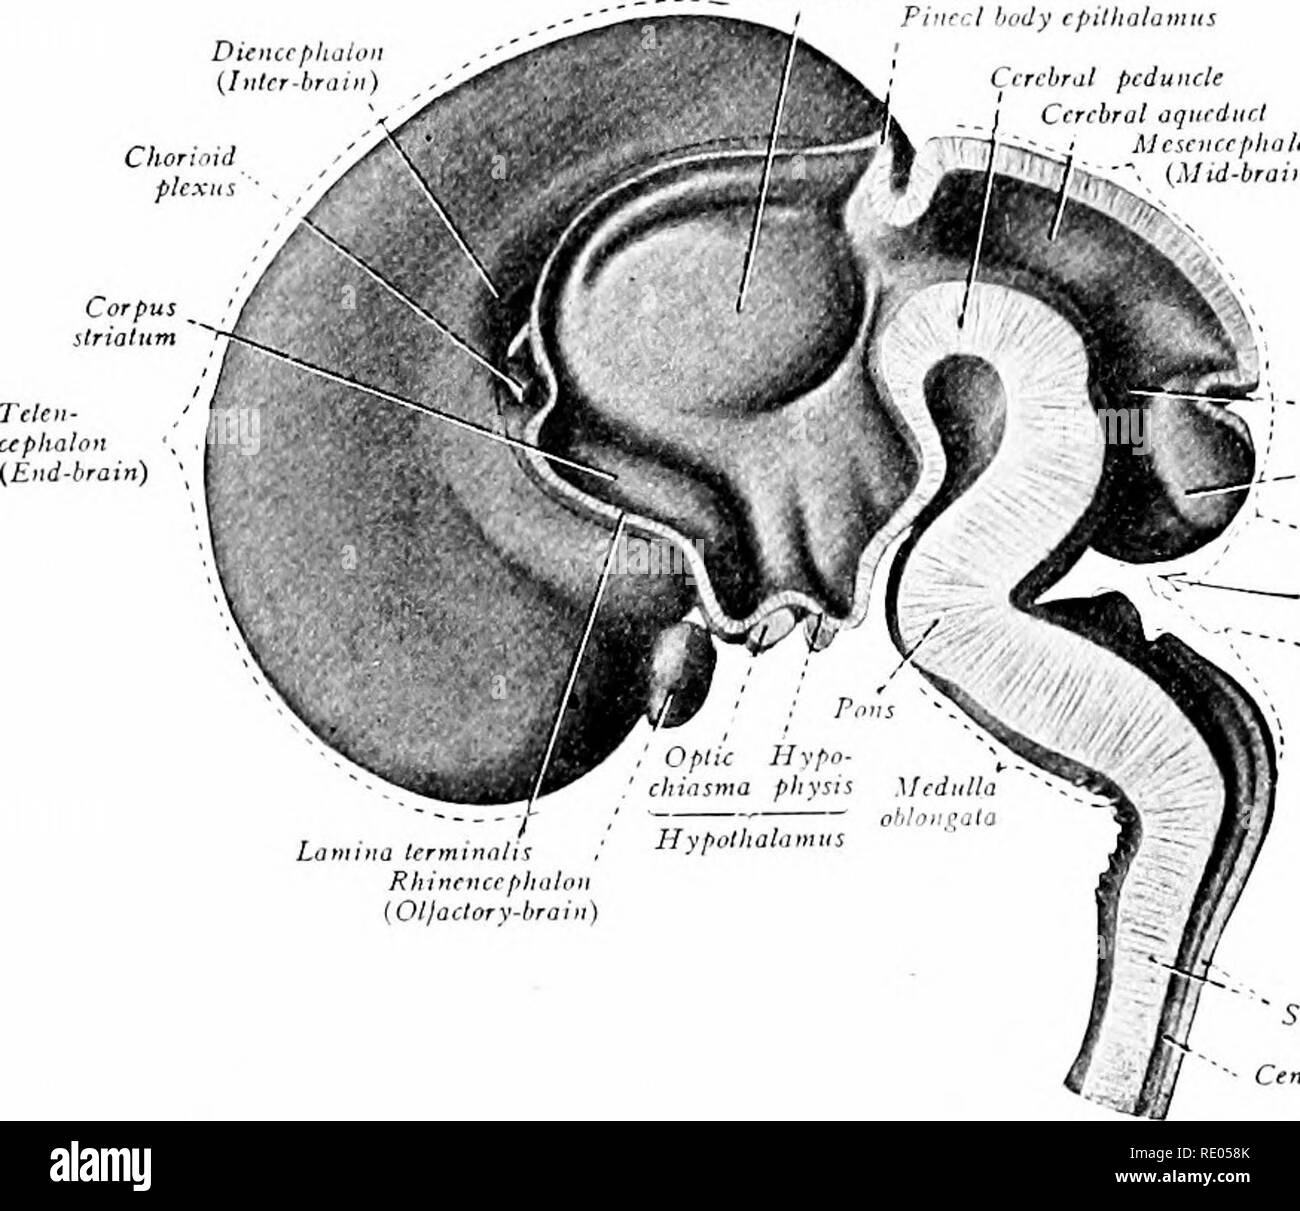

RMRE058K–. Ein Labor Hand- und Lehrbuch der Embryologie. Embryologie. 338 DER MORPHOGENESE DES ZENTRALEN NERVENSYSTEMS Netz der Blutgefäße und eine wichtige interne Sekret produzieren. Gleichrangig mit der Differenzierung der anterior lobe den infundibular Anlage des Diencephalt (Inter-) braiu lpkZs Körper epiihalamus Narbig Zerebrale pedu Nek zerebrale Aquädukt Mesencephalon"<"). RkombemxphaHc isthmus Kleinhirn Metencephaloti {Hind-Gehirn) Rhombischen fossa Myelentepkalon [Ajler - Bmin) spinale Karte zentralen Kanal Abb. 324.- medianen Sagittalschnitt des Gehirns von einem Fötus der dritten Mon

RMPFYB74–. Cunninghams Lehrbuch der Anatomie. Anatomie. PAETS abgeleitet aus dem ZWISCHENHIRN. 617 davon, welche das Aquädukt umgibt, ist direkt kontinuierlich mit der grauen Substanz der substantia perforata posterior und Tuber cinereum, und auf diese Weise kommt es zu der Oberfläche in der Unterseite des Gehirns. Die optic Chiasma kreuzen den Boden vor und markiert die Stelle, wo der Letzteren stetig mit der anterioren Wand des Hohlraums wird. Die vordere Wand des dritten Ventrikels wird durch die Lamina terruinalis, die sich nach oben erstreckt sich von der Optic chiasma gebildet. Die anteriore com-missure, wie es kreuzt von einem